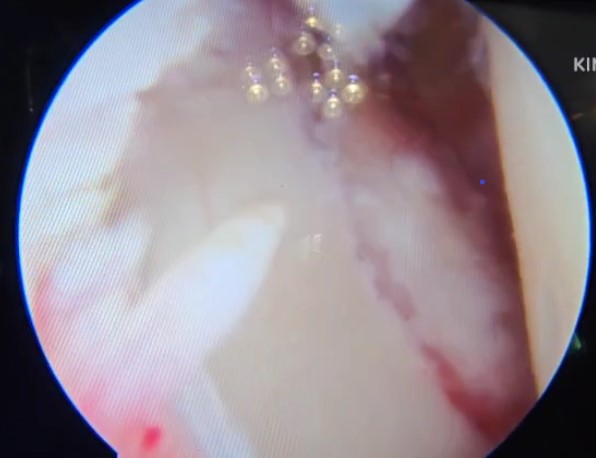

All patients underwent an arthroscopic Bone Block Cerclage procedure for anterior shoulder instability with glenoid bone loss. Four patients with engaging Hill-Sachs lesions underwent concomitant remplissage. The patient is positioned in the beach-chair position. The shoulder and arm are prepared and draped in the standard sterile fashion. Diagnostic arthroscopy is performed through a posterior portal to assess the extent of glenoid bone loss and to confirm the presence of any capsulo-labral deficiency. A tricortical iliac crest autograft of desired size, is harvested using osteotomes, maintaining the concavity of the inner table to match the contour of the glenoid articular surface. A standard anterior portal is established to allow instrument access for debridement and graft placement. The glenoid defect is prepared to obtain a flat, bleeding surface to promote graft healing. An accessory posterior portal is made to pass the glenoid guide jig [figure 1]. The glenoid guide is then introduced through the posterior portal. Under direct visualization, the guide sleeve is positioned on the glenoid face, ensuring that the planned tunnel exits at the centre of the anterior defect. Two parallel guide pins are then drilled from posterior to anterior through the glenoid, spaced appropriately to match the graft size. The drill is removed, and the cerclage passing wires or polypropylene threads are advanced through the tunnels. The bone block - iliac crest autograft - is trimmed to the desired dimensions and predrilled to match the spacing of the glenoid tunnels [Figure 2]. Two high-strength cerclage sutures are loaded into the passing wires and shuttled from posterior to anterior [Figure 3]. The tapes are retrieved through the anterior portal. The bone block is attached to the cerclage tapes and gently introduced through the anterior portal [Figure 4]. Using the tapes as guides, the graft is advanced into position against the anterior glenoid defect. Once seated flush with the native articular surface, the cerclage tapes are tensioned sequentially using the cerclage tensioner device. This step compresses the graft uniformly against the glenoid rim, providing strong fixation without the need for metal screws. The tension is maintained as the locking mechanism is engaged, and the excess tape is cut flush to the bone. The technique sought a flush graft-to-glenoid articular surface and restoration of the glenoid arc. Final arthroscopic inspection confirms the graft’s position and stability [Figure 5]. The glenoid contour is restored, and the construct demonstrated excellent compression and alignment. The capsulo-labral tissue is repaired to the graft using suture anchors to re-establish the soft-tissue restraint. The shoulder is taken through a full range of motion to confirm construct stability. The portals are closed in standard fashion, and a sterile dressing is applied. Post-operatively, the patient is placed in a sling for protection, and a structured rehabilitation program is initiated to restore motion and strength gradually - passive abduction and forward flexion to 90 degrees started on day one, pendulum exercises at four weeks, active range of motion exercises at six weeks and weight training at three months. The bone block cerclage technique offers stable fixation, facilitates graft incorporation, and eliminates hardware-related complications.

Figure 5